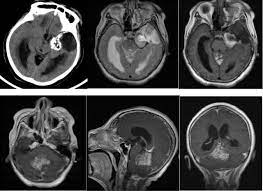

典型的CT表现是脑室内不均匀的高密度肿块,伴有中等对比增强。MRI T1加权像表现为轻度高信号,T2加权像表现在某种程度上更加多变。使用钆后通常增强。可能难以通过MRI区分中央神经细胞瘤、脑室外神经细胞瘤与更常见的病灶(像高级别胶质瘤)。

大多数中央神经细胞瘤是多囊性肿瘤且有钙化,以宽基底附着在脑室上外侧壁上。它们通常位于侧脑室或三脑室,附着于室间孔附近的透明隔或脑室壁上。但通常不会出现在侧脑室枕角或颞角。